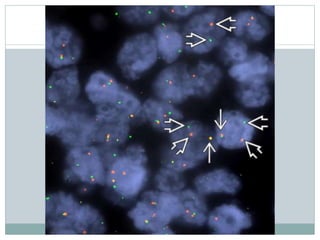

• #42 In this fluorescence in situ hybridization (FISH) preparation, dual color break-apart probes are used for the EWSR1 gene on chromosome 22. In the nucleus of a tumor cell, split red and green signals, instead of a fused yellow one , indicate a translocation involving EWSR1.

• #43 Soft tissue ES shows rearrangement of the EWSR1 gene in 92% of cells analyzed using a dual-color, break-apart probe. A fused signal is yellow or has touching signals, while the 5' and 3' split signals are red and green , indicating rearrangement. There is generally 1 normal EWSR1 allele and 1 split allele per nucleus.